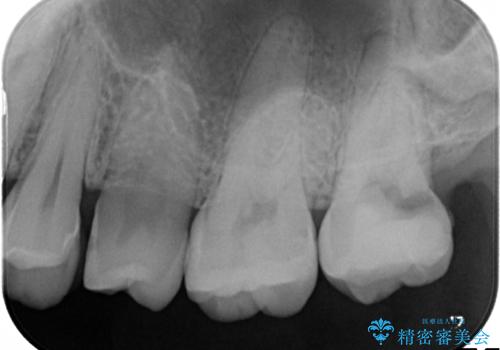

奥歯が感染をおこし強い痛みを出してしまっていたため、顕微鏡を用いた根管治療をおこない根管内を洗浄した後かぶせ物を製作しました。

- 仮歯を製作し、根管治療をおこなう

→土台を築造後、かぶせ物を製作する